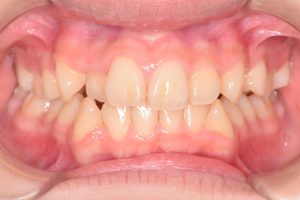

正面

0000000001

0000000022

0000000073